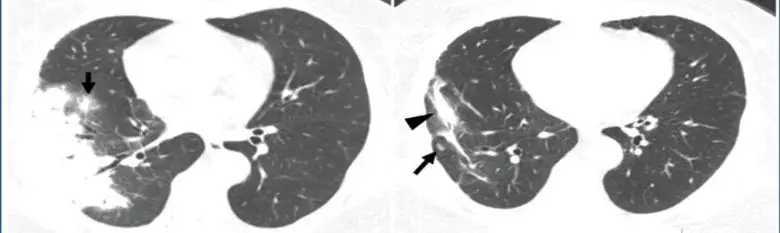

肺结核征象同样多变 ,常见为周围卫星灶及磨玻璃样改变,易被误诊为其他感染性疾病,需要实验室检查支持如T-SPOT等进行诊断。

1599962719309_182fe9c6j00qgk3gi000xd200li008vg00g2006m.jpg

图8 肺结核表影像学表现

结核空洞通常周围为薄壁空洞、壁均匀、细支气管受累、肺野内出现树芽征。

1599962817714_9eba0799j00qgk3gi001ad200lo009eg00g2006y.jpg

图9 左下肺结核空洞表现